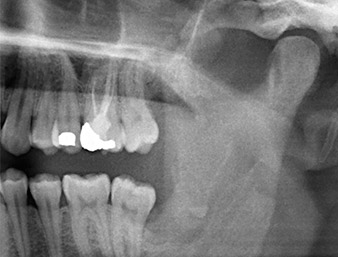

Ya en la ortopantomografía, se constató que había un resto radicular de la región 38 muy cerca del nervio alveolar inferior (figura 1). La raíz se había fracturado durante la osteotomía, pero el primer odontólogo que había tratado al paciente no había extraído esta debido a la presencia de dolor durante la operación.

La anamnesis del paciente era favorable (no fumador, 26 años) para garantizar el éxito de la aplicación. Como la ortopantomografía mostró que el resto radicular se encontraba muy cerca del nervio alveolar inferior, se realizó también una tomografía volumétrica digital (6).